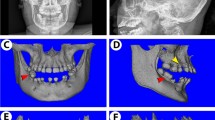

To investigate whether KDM4B affects age-related oral bone loss, we obtained OMSCs from the mandibles of both young and aged mice, respectively, and confirmed that Kdm4b expression is downregulated in aged OMSCs compared with young OMSCs as determined by quantitative reverse transcriptase polymerase chain reactions (qRT-PCR) (Fig. 1a). For further studies, we performed experiments using Prx1Cre;Kdm4bf/f (Kdm4bf/f) mice, which specifically delete the expression of KDM4B in MSCs as described in our previous study.3,23 Knockout efficiency in OMSCs was confirmed by qRT-PCR (Fig. 1b). To find out whether KDM4B regulates age-related oral bone loss, we harvested the mandibles from 3-, 12-, and 18-month-old Prx1Cre;Kdm4bw/w (Kdm4bw/w) and Kdm4bf/f mice and examined with Micro-computed tomography (µCT). 3-D mandibular bone construct at the 1st molar region revealed that 18-month-old Kdm4bf/f mice presented a significant decrease in the cortical bone thickness (Cb.Th) compared with age-matched Kdm4bw/w mice; however, there was no significant difference in Cb.Th at 3- and 12-month of age (Fig. 1c, d). BMD of trabeculae and bone volume fraction (BV/TV) of mandibles were also attenuated in Kdm4bf/f mice than in Kdm4w/w mice with advanced aging (Fig. 1e). Consistently, we also observed a significant decrease in trabecular bone number (Tb.N) and elevated trabecular spacing (Tb.Sp) in Kdm4bf/f mice compared to its age-matched control mice at 18-months old (Fig. 1f). Histological analysis revealed the number of osteoblasts (Ob.N/BS) and osteoblast surfaces (Ob.S/BS) relative to total bone surface were decreased in Kdm4bf/f mice in 12- and 18-month old, compared to their controls (Fig. 1g, h). In contrast, tartrate-resistant acid phosphatase (TRAP) staining demonstrated that osteoclasts’ activity and number were unaffected by the deletion of Kdm4b in OMSCs (Fig. 1i, j). Previous studies report that MSCs from long bones could differentiate into both osteoblasts and adipocytes, but the lineage commitment to each cell type is mutually exclusive.24,25 Thus, we explored whether loss of bone formation in aged Kdm4bw/w and Kdm4bf/f mice led to fat accumulation in the marrow space of the mandible. Although adipogenesis in mandibles is very weak compared with long bones, our immunostaining exhibited a higher fat cell density and fat cell fraction in the mandibles of 18-month-old Kdm4bf/f mice than 18-month-old Kdm4bw/w mice (Fig. 1k, l). Taken together, our data infer that loss of KDM4B in OMSCs promotes aging-related oral bone loss.

Deletion of Kdm4b in OMSCs enhances age-related bone loss and adipose accumulation in mandible. a qRT-PCR showing mRNA levels of Kdm4b in OMSCs isolated from young and aged mice. **P < 0.01. n = 5. b mRNA expression level of Kdm4b in OMSCs isolated from Prx1Cre;Kdm4bw/w (Kdm4bw/w) and Prx1Cre;Kdm4bf/f (Kdm4bf/f) mice. **P < 0.01. n = 6. c Three-dimensional (3-D) images of mandibles constructed by µCT from Kdm4bw/w and Kdm4bf/f mice at 3-, 12- and 18-month old, respectively. Scale bar, 1 mm. n ≥ 14 per group. Red dashed lines indicate the region of trabecular bone analysis performed, and the arrows indicate the limits for cortical thickness analysis. d Quantitative measurements of Cb.Th in mandibles from Kdm4bw/w and Kdm4bf/f mice. **P < 0.01; #P < 0 .05. n ≥ 14 per group. e BMD and BV/TV measurements by µCT of mandibular bone from Kdm4bw/w and Kdm4bf/f mice. **P < 0.01; ##P < 0.01. n ≥ 14 per group. f Tb.N and Tb.Sp quantification by µCT of mandibles from Kdm4bw/w and Kdm4bf/f mice. *P < 0.05; **P < 0.01; ##P < 0.01. n ≥ 14 per group. g Histological hematoxylin and eosin (H&E) staining of trabecular bones in mandibles from Kdm4bw/w and Kdm4bf/f mice. Scale bar, 30 µm. n ≥ 12 per group. h Histological data analysis of osteoblasts number and osteoblasts surface/bone surface (Ob.N/BS and Ob.S/BS, respectively) in mandibles from Kdm4bw/w and Kdm4bf/f mice. **P < 0.01; ##P < 0.01. n ≥ 12 per group. i TRAP staining of osteoclasts in mandibles from Kdm4bw/w and Kdm4bf/f mice. Scale bar, 40 µm. n ≥ 12 per group. j Quantitative data of Oc.N/BS and Oc.S/BS, respectively, from Kdm4bw/w and Kdm4bf/f mice. n ≥ 12 per group. k Histochemical detection of Perilipin-1 expression in mandibles from Kdm4bw/w and Kdm4bf/f mice. Scale bar, 30 µm. n ≥ 12 per group. l Density of adipocytes and the fat fraction of adipose tissue in mandibles from Kdm4bw/w and Kdm4bf/f mice. **P < 0.01; ##P < 0.01. n ≥ 12 per group